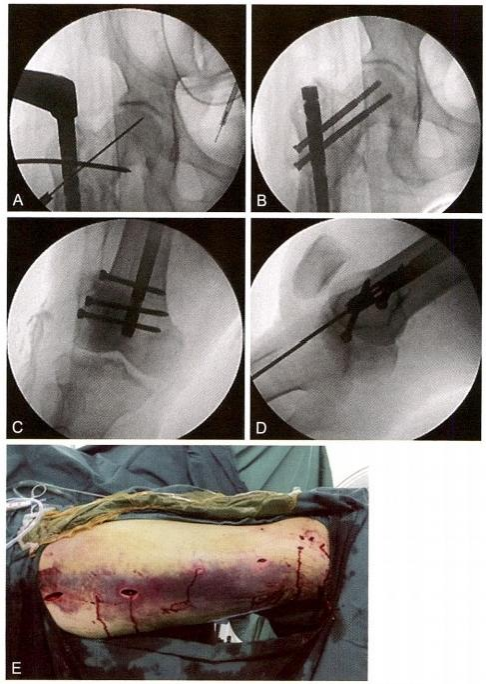

撬拔技术:先用4mm 克氏针经皮插入,纠正近端前屈、外展、外旋, 然后开口定位(图12-3)。

复位手指技术:开口后用“复位手指”器进行复位(图12-4)。

在复位手指引导下插入导针(图12-5A) 。 在复位手指配合下,透视 确定需要推顶的部位(图12-5B) 。 顶棒技术:经皮插入克氏针,推顶移 位骨块(图12-5C), 并将导针插入中间骨块髓腔(图12-5D)。 采用同样 方法,用克氏针推顶远端骨块,并插入导针(图12-5E 、F)。

图12-5 插入导针及推顶骨块。 A. 插入导针;B. 透视确认需要推顶的位置;C. 推 顶复位骨块;D. 将导针插入中间骨块;E. 撬拨复位远端骨块;F. 导针进入远端髓腔;G. 近端骨块复位情况;H. 远端骨块复位情况

扩髓后插入髓内钉并行上、下锁定固定(图12-5G), 从皮钉可以看 出,均在微创闭合复位下进行(图12-5H)。

从缝合伤口中可以看出,复杂骨折完全在闭合下复位(图12-6)。

图12-6 术毕情况,闭合复位切口